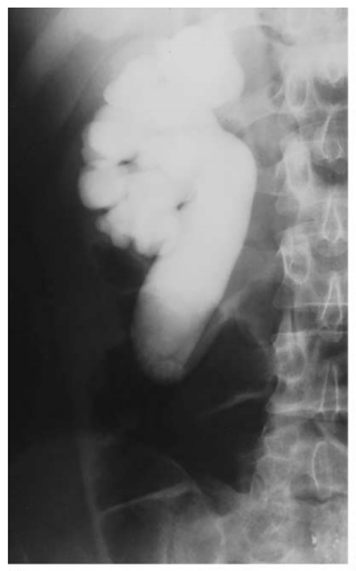

medullary sponge kidney

neurogenic bladder

papillary necrosis